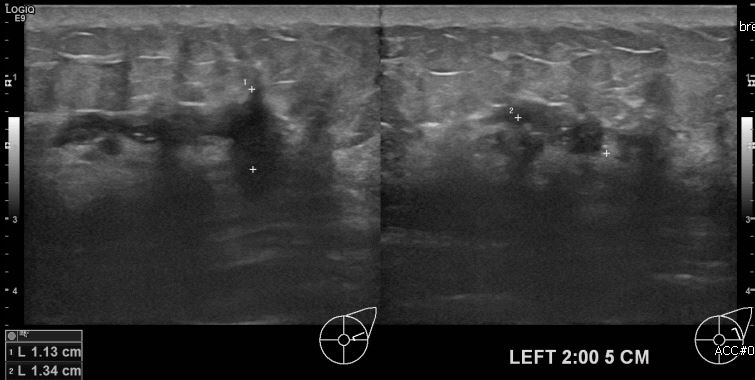

좌측유방의 멍울로 내원하신 30대 여성분으로 본원 초음파상 좌측 2시 방향에 5cm

거리에 의심스러운 멍울 조직검사 시행하여 좌측 침윤성 유관암 진단되었습니다.